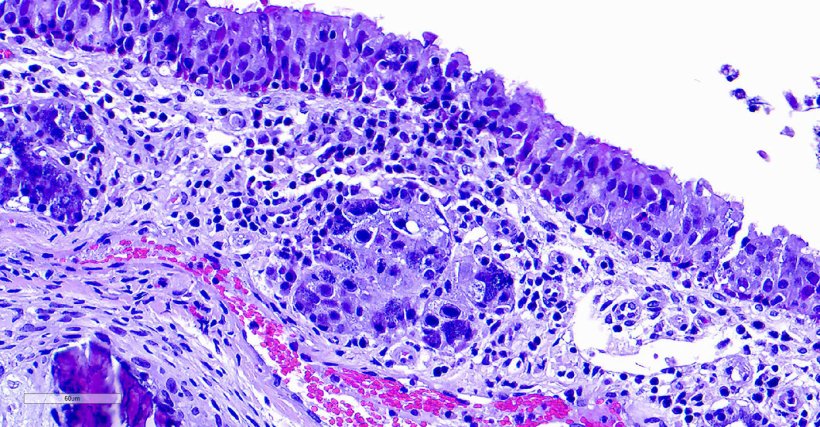

Inclusion body rhinitis (IBR) is caused by porcine cytomegalovirus (PCMV). This disease was originally named “inclusion body rhinitis” based on the histopathological characteristics of the disease. These animals exhibit basophilic intranuclear inclusion bodies primarily in the submucosal glands, although such inclusions can also be found in other tissues. Even though PCMV is widespread and highly prevalent in swine populations, its impact on the swine industry remains poorly defined and is often underestimated, partly due to potential interactions with other pathogens.